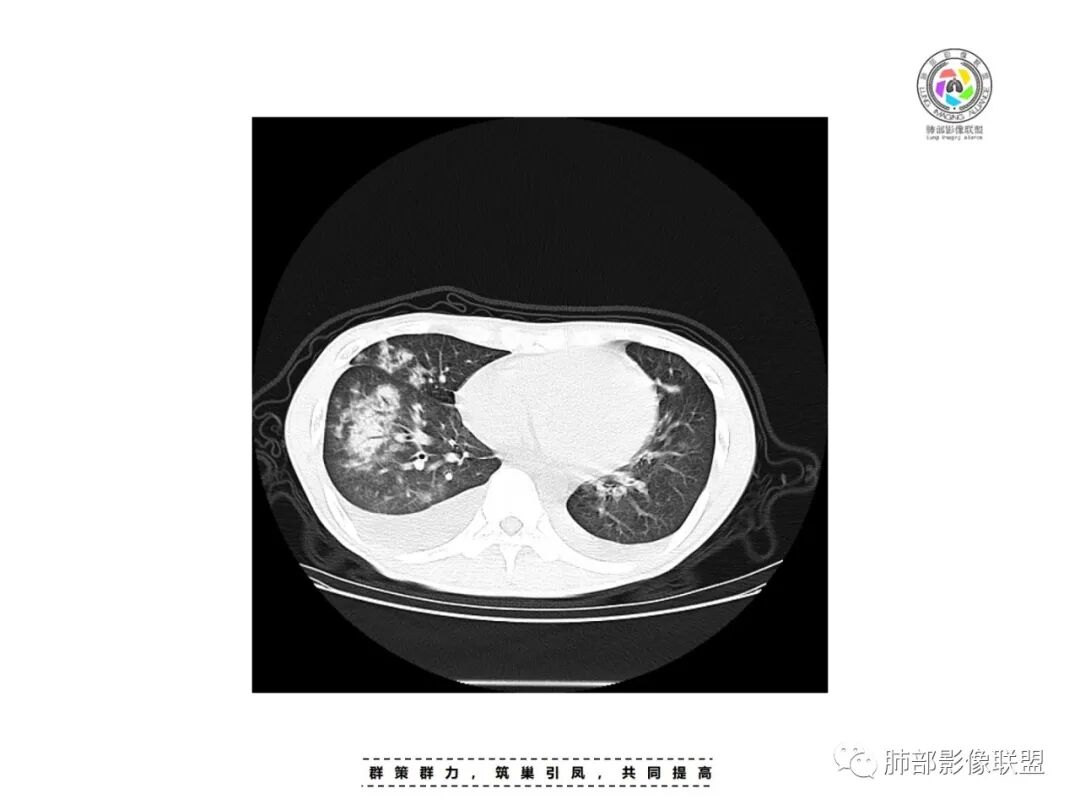

丽:青年男性,双下肢水肿,病史无肺部症状,化验白细胞明显减低;白蛋白低,提示双侧胸腔积液可能低蛋白所致。补体值降低提示自身免疫性疾病,影像见双肺散在结节样,斑片状高密度影及实变密度影,大部分沿支气管血管束分布,以右肺下叶为主,内可见充气支气管征,周围可见磨玻璃密度,并见多发小叶间隔增厚,伴心包少许积液,双肺病变,临床无症状,感染首先除外,结合腮腺病变,双下肢病变及化验检查,综合考虑自身免疫性疾病肺部改变

一切∮随缘:右肺多发大片状实变影,边界模糊,周围可见磨玻璃影,部分可见支气管穿行,支气管壁增厚,支气管扩张,血管束增粗,双肺多发结节,结节分布,以支气管束分布为主,双侧胸腔积液,心包积液,心包密度减低(贫血?),年轻男性,有下肢浮肿,实验室有血象及蛋白减低,考虑:1:病毒性肺炎2:GPA3:淋巴瘤

张延军:双肺多发斑片及结节状高密度影,边缘不清,结节周围伴晕征,前者沿支气管束分布呈实变影,内走形支气管通畅,临近肺组织见大片状磨玻璃影,界不清,中轴间质增厚,影像提示,支气管血管束周围及肺内间质为主病变,临床风免提示,考虑结蹄组织疾病肺内改变

沿支气管血管束分布斑片状更高密度影,部分实变

南边:边界不清,内部支气管通畅

双侧胸腔积液,双下肺斑片状磨玻璃密度影,背景是大片状磨玻璃密度影,密度稍低一些。这个磨玻璃影非常弥漫,没有受局限,胸膜下不是很清楚,内部结构显示清楚,稍实变的区域也是,小叶间隔增厚,中轴间质也增厚。有些病变边缘有收缩,有轻度OP样特点,但是这些病变似乎密度非常均匀。

这类病变首先不是气道来源的,应该是沿间质分布,或者是肺泡腔内的病变。支气管壁周围增厚,磨玻璃影非常均匀,肺泡腔应该也有。